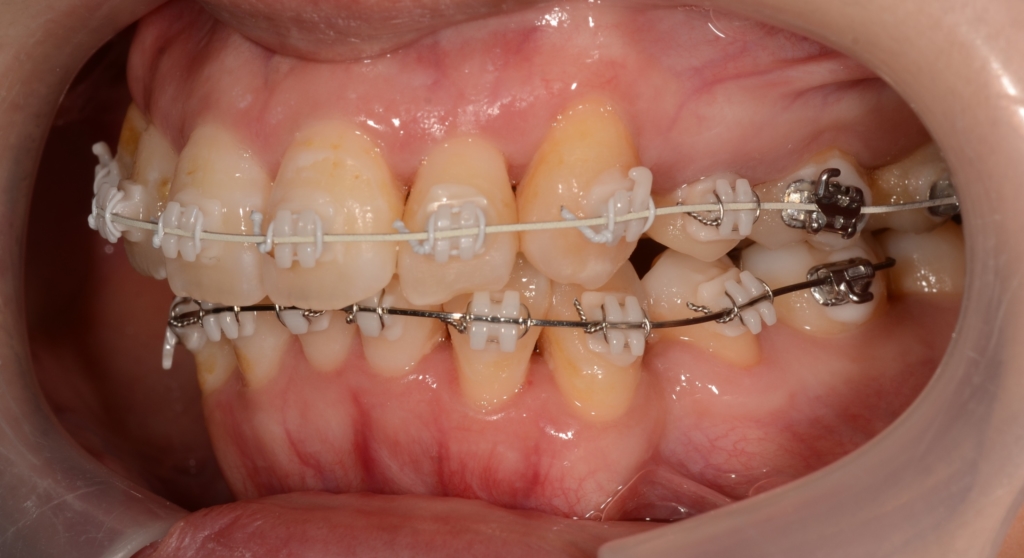

【6か月経過】

上下とも前歯はきれいに並びましたが、左右とも(特に左側)上顎前突(出っ歯)の噛み合わせが残っています

【噛み合わせを良くするために】

上下とも前歯はきれいに並びましたので、次のステップに移ります。

噛み合わせとしては上顎前突(出っ歯)が残っています。 (特に左側)